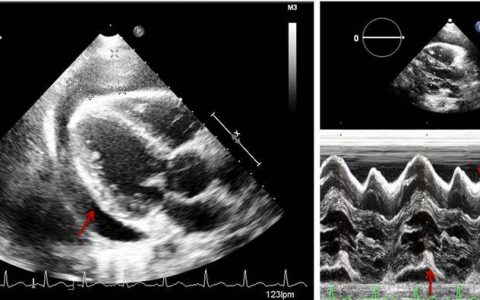

MRI上,最早DWI序列可出现下部桥脑的弥散受限,这可以在患者出现四肢麻痹24小时内看到,该区域此后会显示出T1低信号、T2高信号的改变,典型者轴位图像可表现出三叉样外观。

T1WI和T2WI上的信号演变需要2个星期的时间,偶尔可见钆强化,类似于多发性硬化斑块的急性期。周边纤维(腹外侧纵向纤维),以及脑室周围和软膜下区域通常不受累。类似的信号改变在基底神经节、中脑和皮质下白质中也可出现。

概括而言,受累区域的信号特征包括:

➤ T1:轻度或中度低信号

➤ T2:高信号,保留外周和皮质脊髓束

➤ FLAIR:高信号

➤ DWI:高信号

➤ ADC:信号低或信号丢失

➤ T1 C+(Gd):通常没有增强,但偶尔有病变区域强化的报道